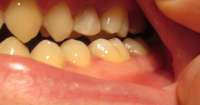

14734355806570.jpg (1325Кб, 1404x1076)

Заделал все верхние зубы, в четверг иду ставить брекеты на "верх". Снизу остался 1 зуб с кариесом, его я удалю и вот эта вот хуйня, что я пытался нарисовать на пике выше. Под зубом 46 живет-растет НЕХ. Я оставил КТ терапевту или как там его, он посмотрел и сказал, что видимо когда то залечили мне тот зуб хуевасто, что-то осталось и вот эта хуйня развилась и по-тихоньку хуует там внутри меня. Сказала, что гарантий никаких на лечение дать не может: мб каналы не "пройдет", мб ухудшится ситуация, мб лечение не поможет и придеться удалять - очень шаткая ситуевина. В чем мой вопрос, казалось бы? А вопрос в том: что блядь делать то мне с этой хуйней? Она где то там внутри, жить не мешает, не чувствуется, не видится(ну кроме как на снимке), зуб я тот делал уже и не помню сколько лет назад. МБ 10-12. Но и она и ортодонт говорят одно и тоже: это бомба замедленного действия, может выскочить в любой момент и будет пиздец. Вроде терапевт сказала, что кость там задета этой хуергой или костная ткань. Что-то типа того.

Варианты следующие:

1. Пока есть месяц-полтора до постановки на нижнюю челюсть заняться зубов, просверлить его, положить "лекарство", временную пломбу заделать, надеяться, что пронесет и ставить брекеты. Но есть шансы, что все накроется пиздой, зуб в итоге хуй сохранишь, все мне там распидорасят и будет у меня дыра. А как же тогда брекет лепить? Слепок то делался под все зубы.

2. Нихера не трогать, ставить брекеты, а заняться через полтора года, когда систему сниму. Надеяться, что пронесет. Деньги пустить на сами брекеты, а когда уже все зубы будут как надо, ровные и тд - заниматься этой хренью. Если тогда уж удалять, то думать там - мост/имплант или что.

3. Есть еще мутный третий вариант это ходить по клиникам с этим моим КТ и спрашивать, кто возьмется мне эту херню лечить и будет уверен в результате. Но чувствую, все будут говорить, что гарантий никаких, давай неси бабки и раскрывай рот.

Встанет это все не меньше 10 тысяч, а я так вангую, что 15 точно отвалить придется и хуй бы с ним, если бы результат был, а так можно 15 отдать и в итоге получить дыру.

Грамотный анон, что делать то мне? В четверг пойду к ортодонту, скажу ему, что сказал терапевт, надо будет решение принимать какое-то. В какую сторону мне смотреть?

Аноним 09/09/16 Птн 19:52:23  514691

14734399434650.jpg (61Кб, 960x720)

14734399434661.jpg (64Кб, 960x720)

>>514662

Грамотный терапевт с микроскопом тебе нужен. На крайняк - апикальная хирургия.

пики из паблика, который чекаю. Кейс одного из докторов. Мб что-то поймешь. Сравни со своей НЕХ и вот что с ней можно сделать

Ты кажется стрелку не на тот зуб показал на своём пике. У тебя там зуб без пломбы даже. кек.

Мосты - хуйня. Избегай их. Только имплант если уж решишь удалять

>>514665